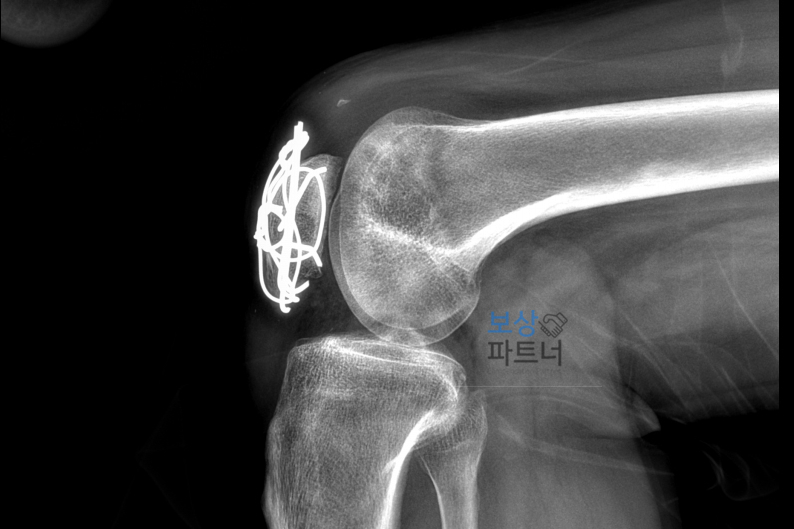

즉시 수술이 진행되었으며, 관혈적 정복술 및 금속 강선을 이용한 내고정술이 시행되었습니다. 안타깝게도 의뢰인께서는 적극적인 재활치료에도 불구하고 무릎을 움직일 때 통증이 지속되었습니다.